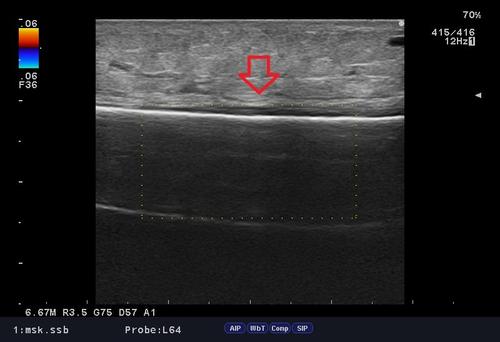

シンスプリント エコー.jpg

当院ではしっかり問診、触診、視診、エコー検査を行い、「なぜ今の不調・症状が出ているのか」という、"根本的な原因"を追求し施術を行っております。